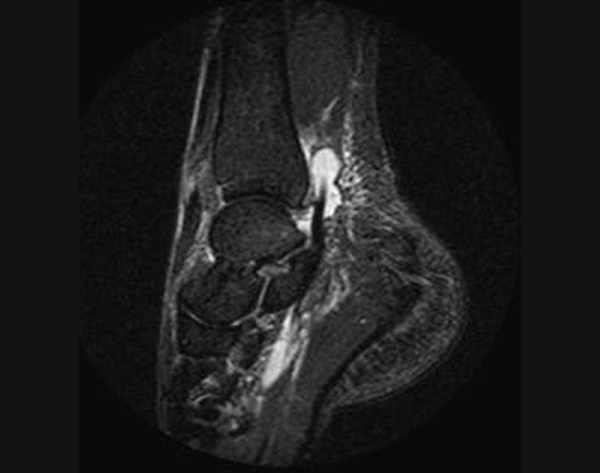

Врачи отмечают, что разрыв связок голеностопа часто сопровождается характерными симптомами, такими как резкая боль, отек и ограничение подвижности. Для диагностики травмы специалисты рекомендуют проводить физикальное обследование, а в некоторых случаях — использовать ультразвуковое исследование или магнитно-резонансную томографию. Эти методы помогают точно определить степень повреждения связок.

Без надлежащего лечения последствия могут быть серьезными. Возможна потеря трудоспособности на срок от одного до двух месяцев. Квалифицированный врач должен в первую очередь исключить перелом или вывих лодыжки. Для этого проводятся следующие диагностические исследования:

При значительном гемартрозе может потребоваться диагностическая пункция. Для определения степени повреждения связок наиболее информативным методом является магнитно-резонансная томография. Этот метод отличается высокой точностью и имеет следующие преимущества:

Однако процедура не подходит для людей с кардиостимуляторами, металлическими имплантатами и аневризмами. При этом лучевая нагрузка отсутствует. Магнитно-резонансный томограф не всегда доступен в медицинских учреждениях, поэтому чаще всего для диагностики разрывов и исключения других травм, таких как переломы и вывихи, используется рентгенография.